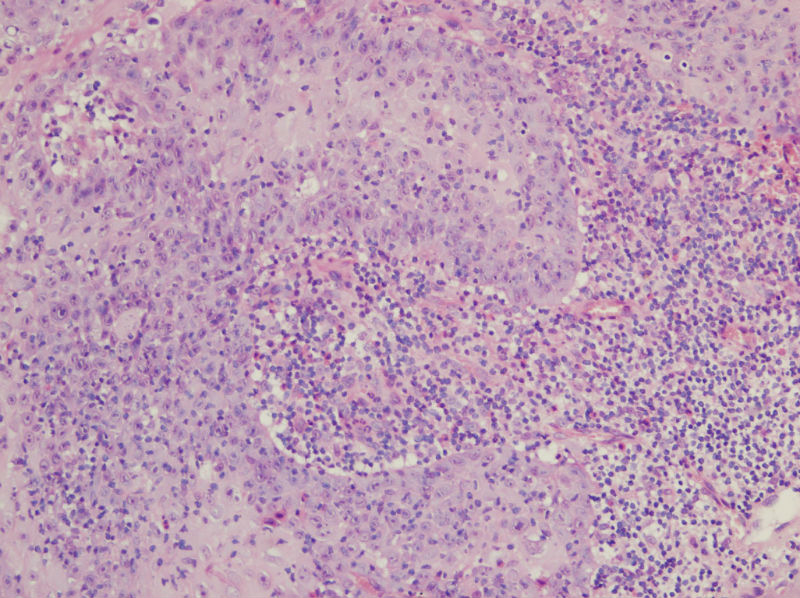

男,45岁,上唇菜花样肿物,请老师指教

图1

高分化鳞癌

倾向于鳞癌,恶黑不除外。